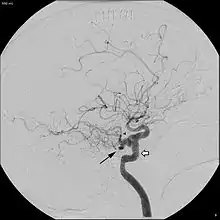

Angiogram demonstrating persistent trigeminal artery, as indicated by the black arrow.